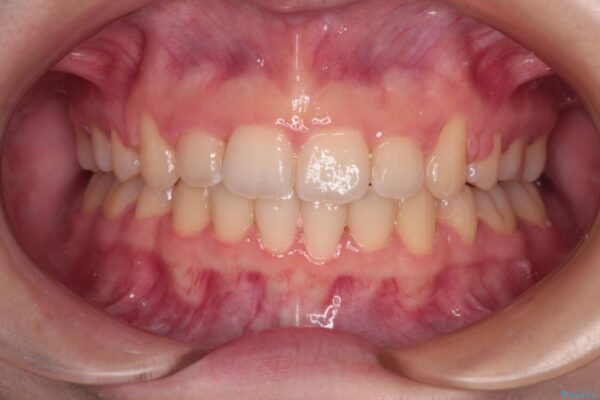

上下の前歯が突出しており、口が閉じにくいとのことで来院された患者様です。

上下前歯が著しく前突している状態であったので、上下左右の第1小臼歯4本を抜歯し、ワイヤー装置にて矯正治療を行うこととしました。

治療前

• 【モニター】口が閉じられない ワイヤー装置での抜歯矯正 治療前画像